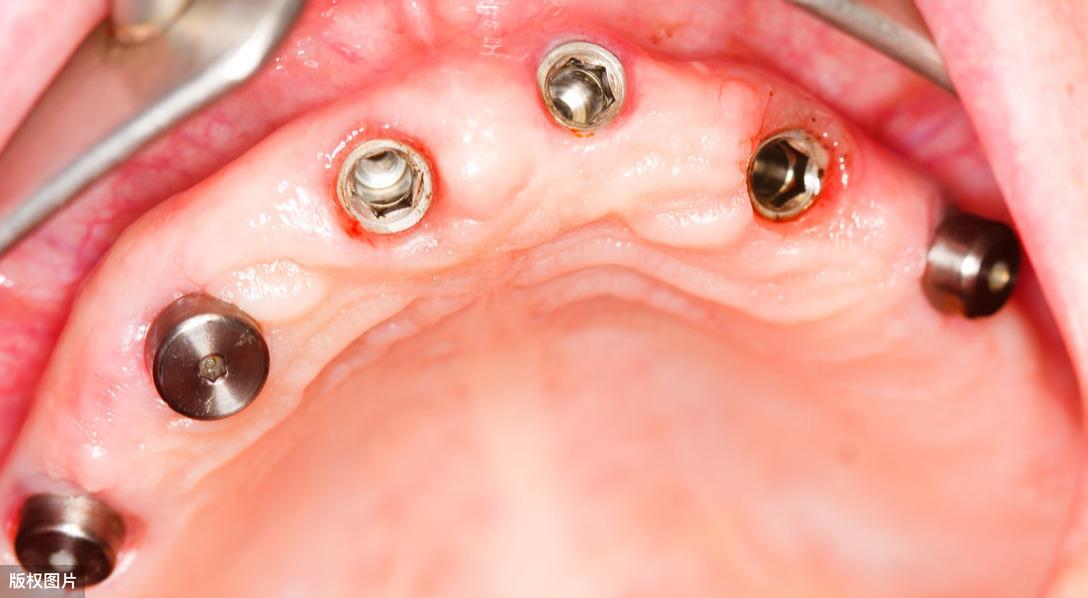

● 種植手術(shù)二期:一期人工牙根(種植體)植入后,需等待4-6個月待種植體與牙槽骨形成“骨結(jié)合”后,開始安裝一個特殊的部件-愈合基臺,它能夠使種植牙穿出牙齦。接下來繼續(xù)等待約1個月左右,待牙齦軟組織成型后,就可以開始制作牙冠了。